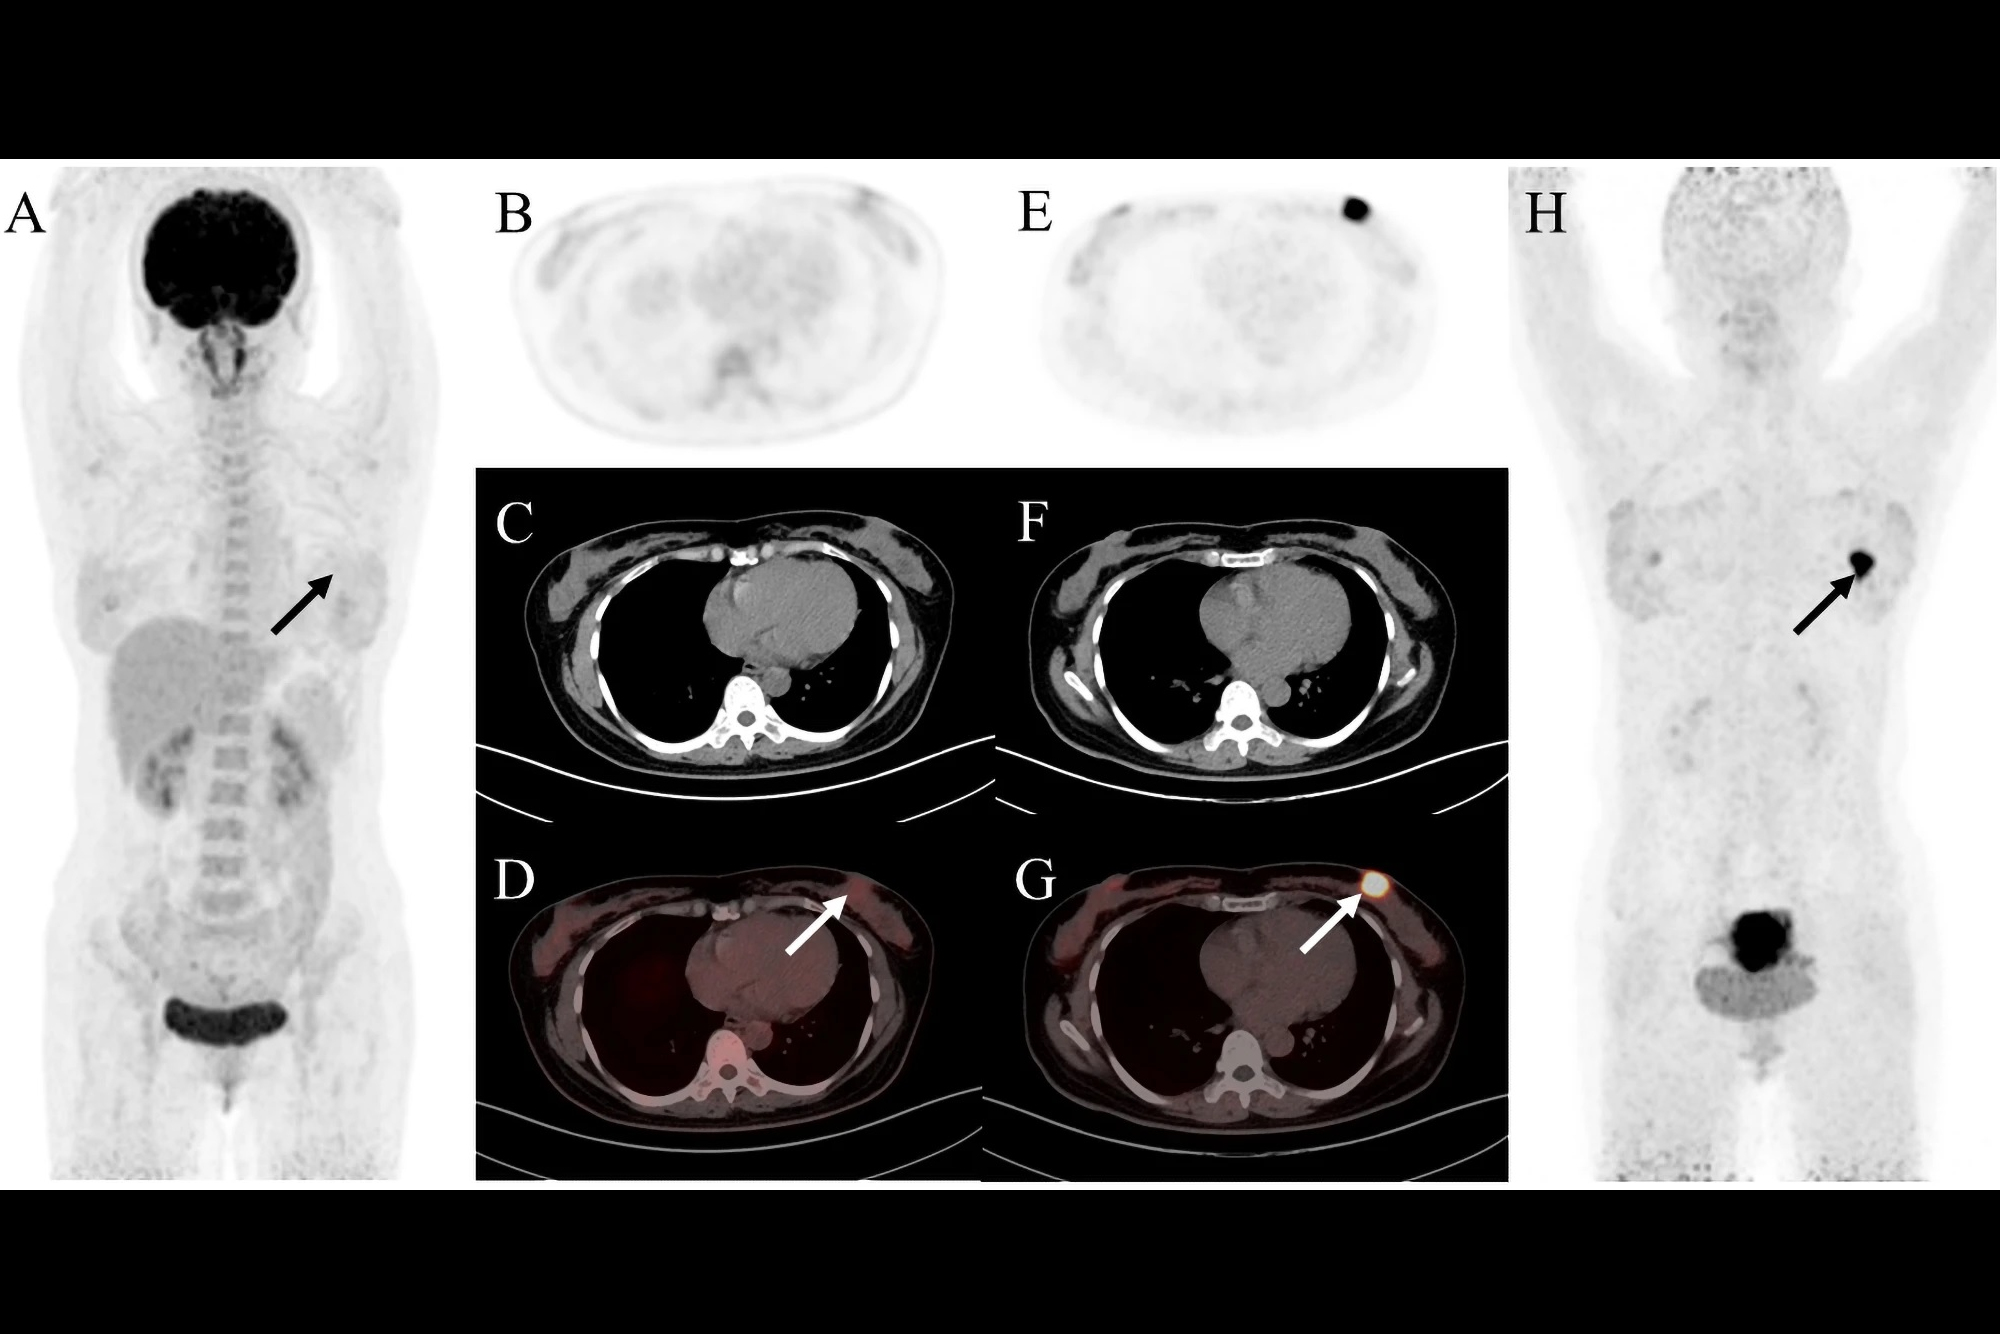

Typical PET (top), PET/CT (middle), and CT and MR (bottom) images of primary tumor obtained using both radiotracers in representative patients (A and B). Tumor is marked by arrows. DWI = diffusion-weighted imaging. Image courtesy of the Journal of Nuclear Medicine.

F-18 FAPI-04 PET/CT identified all patients with PDAC, while F-18 FDG-PET/CT missed one patient, according to the findings. F-18 FAPI-04 tracer uptake was higher than F-18 FDG in primary tumors (10.63 vs. 2.87, p < 0.0001), lymph node metastasis (2.9 vs. 1.43, p < 0.0001), and distant metastases (liver, 6.11 vs. 3.1, p = 0.002; peritoneal, 4.7 vs. 2.08, p = 0.015).

In addition, 14 patients were upgraded and one patient was downgraded due to F-18 FAPI-04 PET/CT scans compared with F-18 FDG-PET/CT, the authors noted.

“Our results demonstrate that F-18 FAPI-04 PET/CT is significantly superior to F-18 FDG- PET/CT in detecting both primary and metastatic lesions,” the researchers wrote.